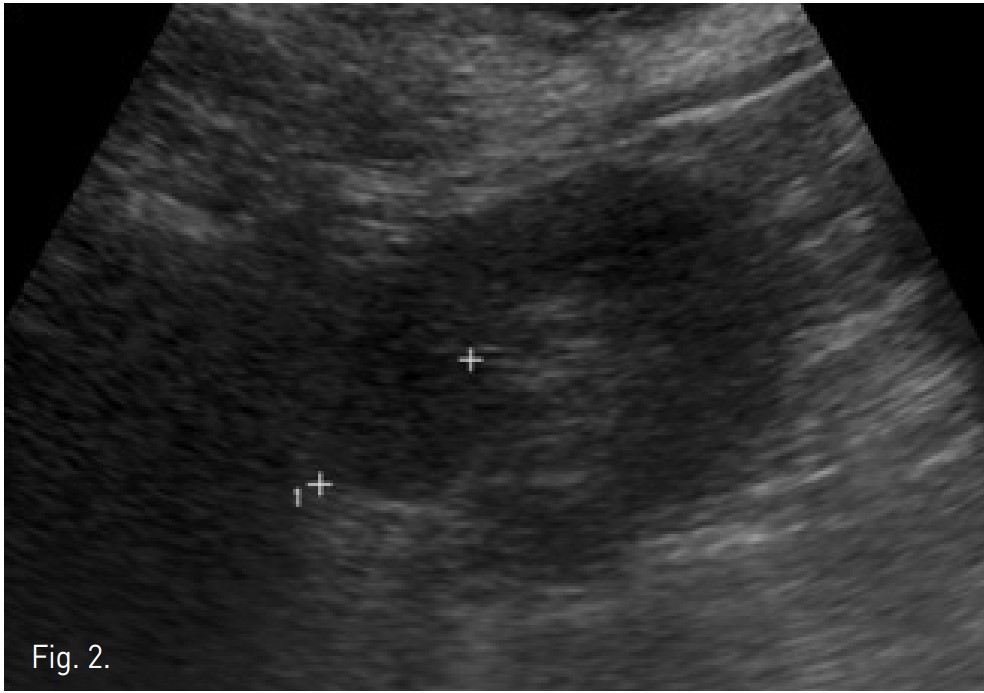

Fig. 2.

Fig. 2. On planning US, RCC in right kidney showed isoechogenicity, which made it difficult to distinguish the mass from renal parenchyma.

CT상 우측 신장 cortex 에 약 3.2cm 크기의 돌출하는 양상의 경계가 좋은 고형 종괴가 있음. 종괴는 신우에 인접해 있었으나 신주위 조직이나 신정맥으로의 침습 소견은 보이지 않았음 (Fig. 1A). 환자가 비수술적 치료를 원하여 고주파열치료를 위해 planning US를 시행하였으나 종양의 에코음영이 신실질과 유사하여 뚜렷이 구별되지 않고 (Fig. 2), 신우에 인접하고 있어 합병증의 위험성이 있고, 고주파 열치료만으로는 충분한 치료가 되지 않을 수 있어서, 동맥 색전술과 고주파열치료의 병합 치료를 하였음. 동맥 색전술과 고주파 열치료를 시행하고 9개월 이후 촬영한 CT에서 우측 신종양은 lipiodol이 compact하게 uptake되었으며 주변에 RF ablation zone이 관찰되고 viable portion이 없는 상태임(Fig. 5).